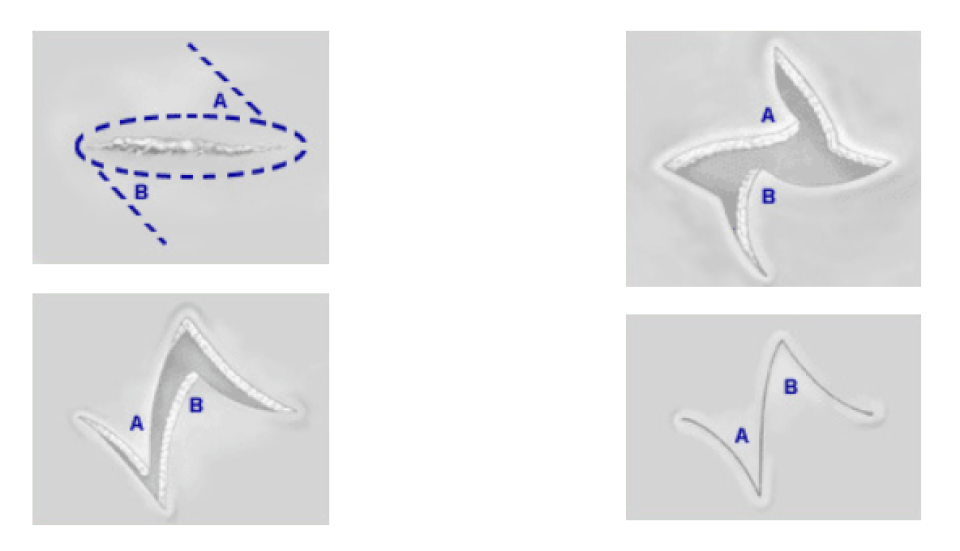

Z-пластика

Z-пластика меняет направление и натяжение в рубце

Z-пластика используется для уменьшения шрама или контрактуры рубца, делая его более комфортным и менее заметным. Метод также может быть использован для изменения положения шрама и уменьшения его «герметичности», чтобы улучшить заживление. Z-пластика выполняется путем поднятия двух соседних кожных лоскутов и транспонирования лоскутов (размещение каждого лоскута там, где был другой — см. иллюстрацию). Дермабразия и лазерная хирургия также могут быть использованы для выравнивания границ рубца и минимизации неровностей кожи.